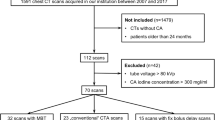

A total of 83 patients met our inclusion criteria and were enrolled in our study, including 42 males and 41 females. Five patients with hemorrhage/infarction following surgical procedures and three patients with serious movement during the CT scanning were excluded from our study. There were no significant differences between the two groups with regard to sex, age, body mass index (BMI), scanning length and hyoid level maximum diameter (Table 1).

This study was approved by the local ethical committee of the Second Affiliated Hospital of Soochow University. The study protocols were performed in accordance with the approved guidelines and regulations. A total of 91 consecutive pediatric patients were enrolled in our current study from January 2016 to January 2017, and 83 participants (42 males/41 females, age range from 10 to 16 years old) met our inclusion criteria and received a head and neck CTA scan. Informed consent documents were obtained from all the enrolled participants and their legal representatives.

General Information

For the inclusion criteria, children who suffered from suspected cerebral ischemic diseases were eligible for our study, which included headache, dizziness, nausea, vomiting, numbness, weakness or obstacles, walking instability, and speech problems. The exclusion criteria were as follows: (1) patients with severe heart, liver or renal insufficiency; (2) allergy to iodine CM; (3) prior surgery with intracranial implants, aneurysm clipping or embolization; and (4) a BMI ≥ 25 kg/m2.